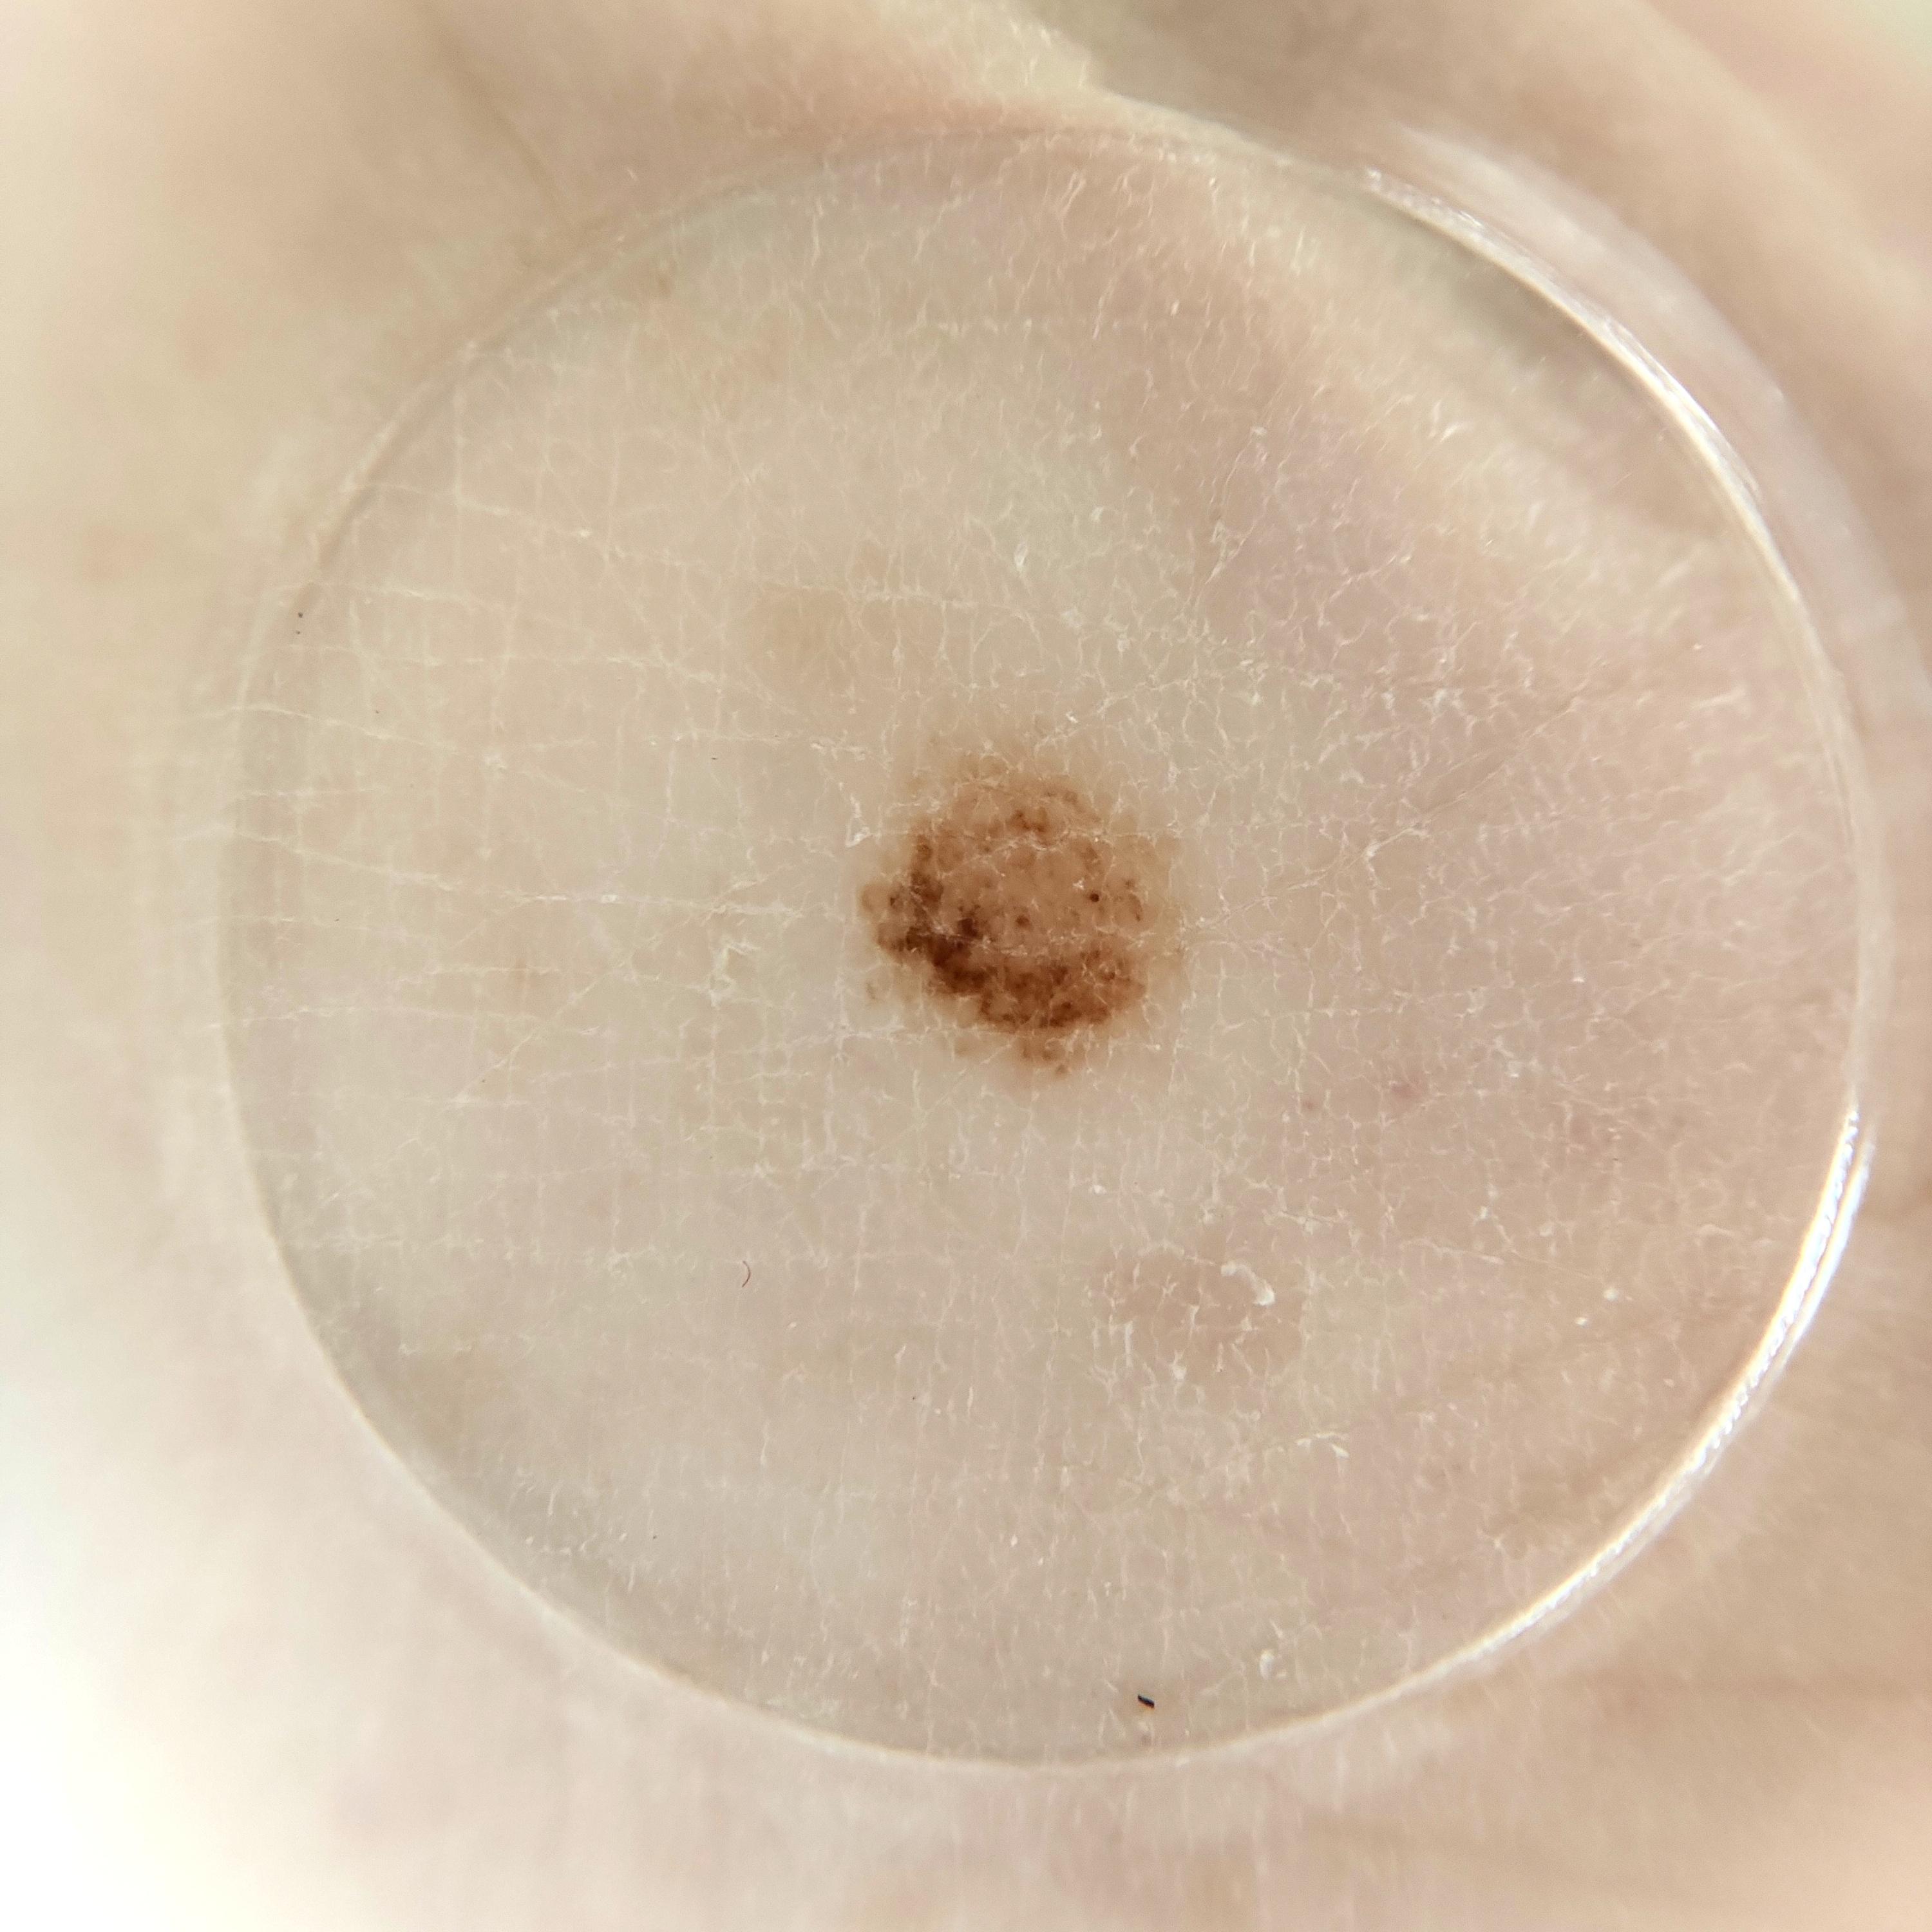

Field Value

acquisition_day 225

age_approx 50

anatom_site_1 Lower extremity

anatom_site_general lower extremity

concomitant_biopsy False

diagnosis_1 Benign

diagnosis_confirm_type single image expert consensus

family_hx_mm True

image_manipulation instrument only

image_type dermoscopic

lesion_id IL_3192179

patient_id IP_8159579

personal_hx_mm True

sex female